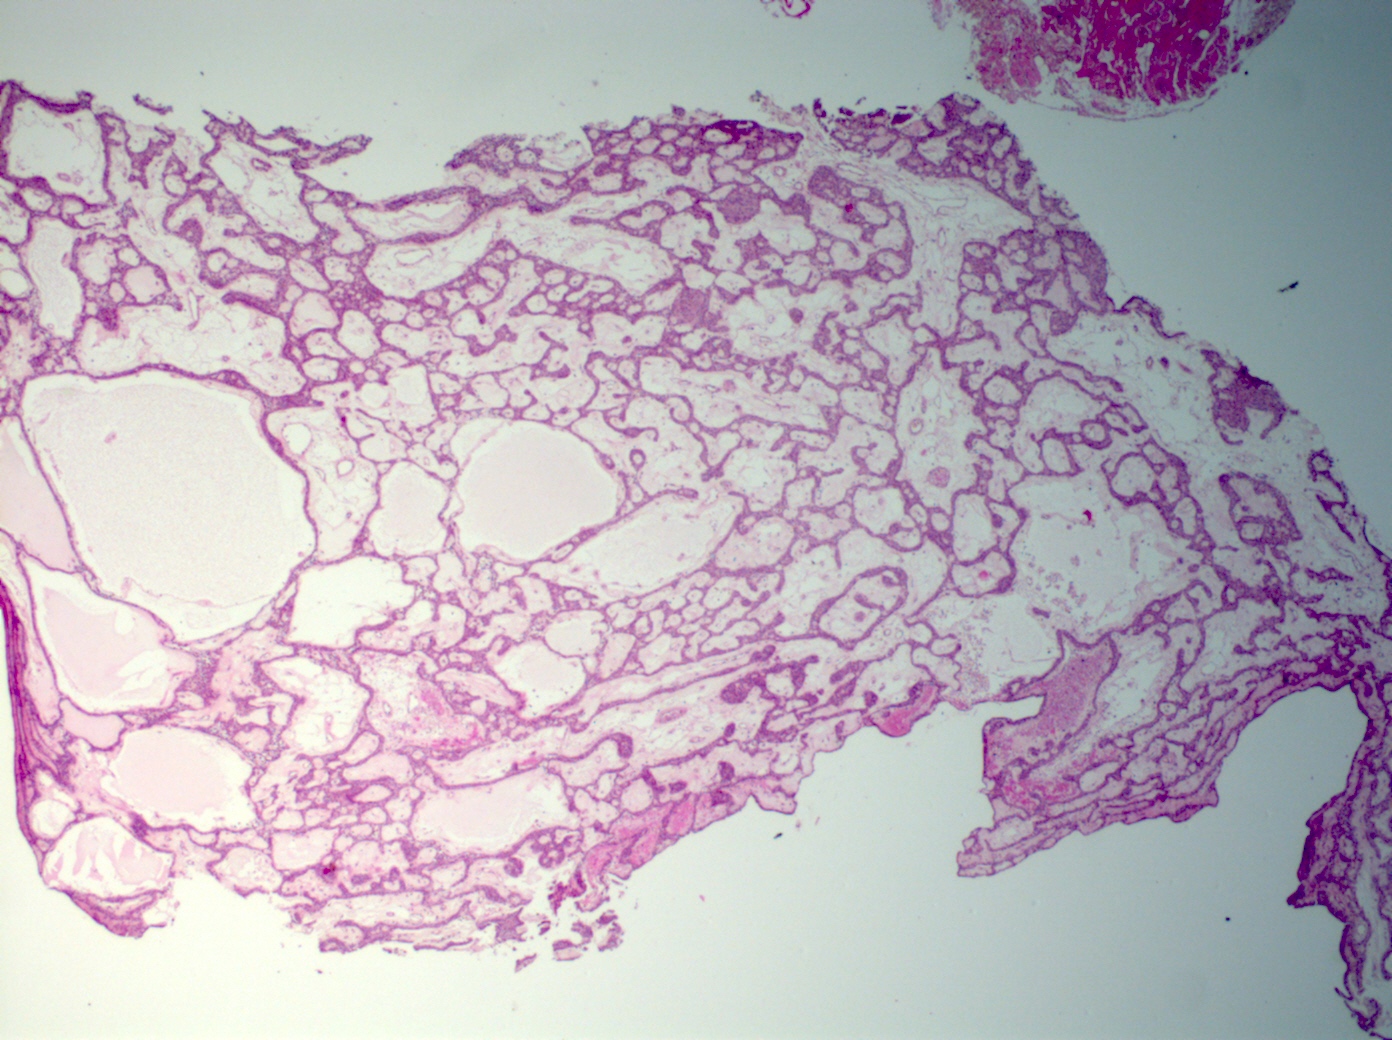

Microscopic (histologic) description

- Tumors may be single or multifocal

- Bilayered strands or ribbons or anastomosing cords or branching tubules

- Canalicular to cystic spaces between the cell strands; trabecular features

- Lack of an outer layer of myoepithelial cells

- May infiltrate capsule and show extracapsular tumor islands (including in the normal salivary gland / multiple tumors)

- Often cystic change

- Well vascularized, loose stroma; possibly sclerotic; perivascular eosinophil cuffs

- Luminal or stromal histiocytes (foamy, lipofuscin, hemosiderin), luminal hemorrhage, degenerated / infarcted stroma (Head Neck Pathol 2015;9:181)

Microscopic (histologic) images